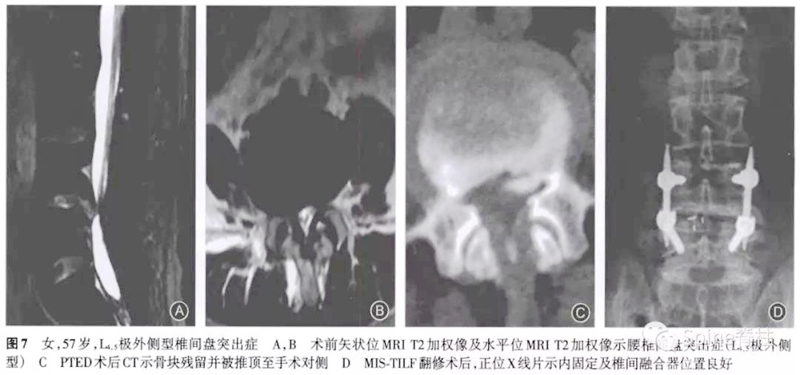

所有7例患者在经皮内镜手术中均进行了椎间孔成形操作。5例为术后立即出现症状,1例为术后1周出现症状,1例为术后1个月出现症状。经保守治疗后,1例患者症状好转拒绝手术,2例出现对侧的刺激症状,余4例均为原症状加重。其中因残留骨块刺破硬膜囊出现脑脊液漏者2例,残留骨块损伤神经引起下肢肌力下降1例。术后CT提示5例骨块在椎问孔成形同侧,2例在对侧。

术后至翻修时间最短为2d,最长为3个月。翻修术式:2例为椎间盘镜手术,1例为可动式椎间盘镜手术,1例为小切口开窗减压术,1例为经皮内镜手术,1例为微创经椎间孔入路腰椎椎体间融合术。